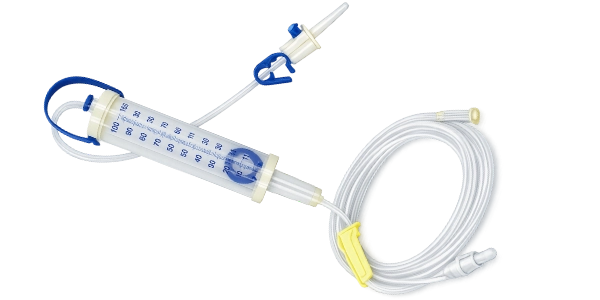

The Measured Volume IV Set (Burette Set) is specially engineered to ensure precise and controlled delivery of intravenous fluids and medications. Featuring a calibrated burette chamber, it allows accurate measurement of fluid volume, making it ideal for pediatric, neonatal, and critical care applications.

Our Measured Volume IV Sets are available in multiple variants to meet different clinical requirements. Each unit is individually packed in sterile, tamper-proof packaging to ensure safety, hygiene, and ease of handling. Designed for convenience and reliability, our packaging supports efficient storage, transportation, and immediate use in medical environments.